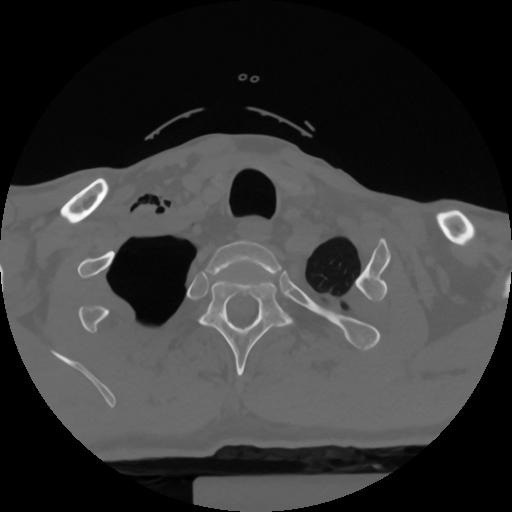

12 P.BLANDAS,,Vol,0.5,P.BLANDAS,,